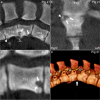

Background: Computed tomography (CT) is used to evaluate body composition and limb osteochondrosis in selection of breeding boars. Pigs also develop heritably predisposed abnormal curvature of the spine including juvenile kyphosis. It has been suggested that osteochondrosis-like changes cause vertebral wedging and kyphosis, both of which are identifiable by CT. The aim of the current study was to examine the spine from occiput to sacrum to map changes and evaluate relationships, especially whether osteochondrosis caused juvenile kyphosis, in which case CT could be used in selection against it. Whole-body CT scans were collected retrospectively from 37 Landrace or Duroc boars with poor back conformation scores. Spine curvature and vertebral shape were evaluated, and all inter-vertebral, articular process and rib joints from the occiput to the sacrum were assessed for osteochondrosis and other lesions.

Results: Twenty-seven of the 37 (73%) pigs had normal spine curvature, whereas 10/37 (27%) pigs had abnormal curvature and all of them had wedge vertebrae. The 37 pigs had 875 focal lesions in articular process and rib joints, 98.5% of which represented stages of osteochondrosis. Five of the 37 pigs had focal lesions in other parts of vertebrae, mainly consisting of vertebral body osteochondrosis. The 10 pigs with abnormal curvature had 21 wedge vertebrae, comprising 10 vertebrae without focal lesions, six ventral wedge vertebrae with ventral osteochondrosis lesions and five dorsal wedge vertebrae with lesions in the neuro-central synchondrosis, articular process or rib joints.

Conclusions: Computed tomography was suited for identification of wedge vertebrae, and kyphosis was due to ventral wedge vertebrae compatible with heritably predisposed vertebral body osteochondrosis. Articular process and rib joint osteochondrosis may represent incidental findings in wedge vertebrae. The role of the neuro-central synchondrosis in the pathogenesis of vertebral wedging warrants further investigation.